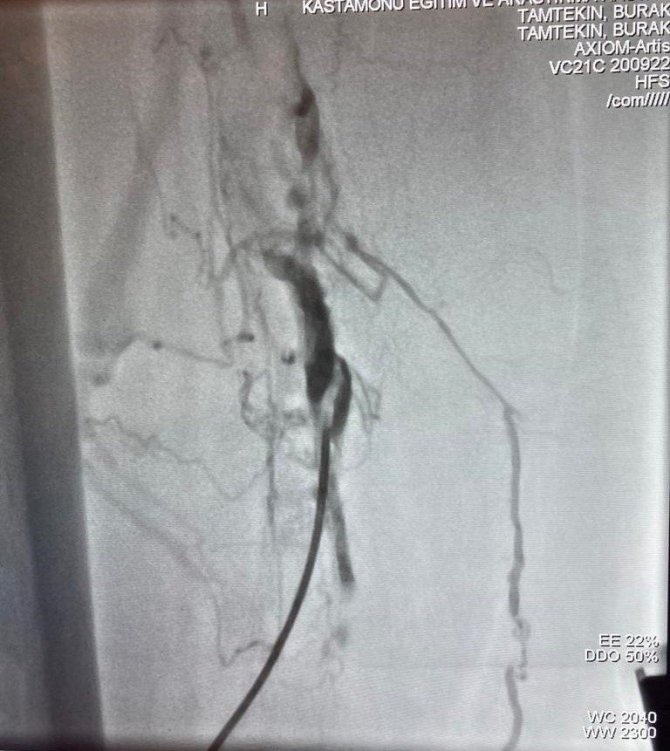

Kastamonu Eğitim ve Araştırma Hastanesi'ne bacak toplardamarları taze pıhtılarla dolu, ileri derecede bacağının şiş ve yürüyemez bir şekilde Kalp Damar Cerrahisi Bölümü gelen 77 yaşındaki Hakan Ural, Kalp Damar Cerrahisi Öğretim Üyesi Op. Dr. Burak Tamtekin tarafından Kastamonu'da ilk defa uygulanan ameliyatsız bir yöntemle toplardamarda oluşan pıhtı çıkarma işlemi yapıldı.

KEAH Kalp Damar Cerrahisi Bölümü A.B.D. Öğretim Üyesi Dr. Burak Tamtekin ve ekibi, 77 yaşında yaşlı bir hastanın bacakta oluşan pıhtının önce kalbe, daha sonra akciğere atması sonucu hayati tehlikesi oluşabilecek hastaya, herhangi bir kesi yapılmadan, narkoz verilmeden, anjiyo yöntemi ile risksiz bir şekilde, toplardamarda oluşan pıhtı çıkarma işlemi yaptı.

Ameliyatsız yöntemle ilk kez böyle bir operasyon yapıldığını söyleyen Tamtekin, "İleri derecede bacağının şiş ve yürüyemez bir halde hastanemize gelen 77 yaşındaki Hakan amcanın bacağının şiş ve yürüyemez bir durumda olduğunu gördük. Yaptığımız ilk muayenesinde bacak toplardamarlarında oluşan pıhtıları gördük. Bacakta oluşan pıhtıları çıkarmak için öncelikle karın içine bir filtre yerleştirildik. Daha sonra pıhtı dolu damarın içine girip, bacakta biriken pıhtıları özel bir aygıtla parçalayıp dışarı çıkardık. Narkoz verilmeden anjiyo yöntemiyle yaptığımız bu başarılı operasyonla akciğere pıhtı atmasını da bu uyguladığımız yöntemle önlenmiş olduk. Kastamonu'da ilk kez yapılan bir buçuk saat süren anjiyo uygulaması sırasında Hakan amcayla hoş sohbette bulunduk. Ekip olarak biz işimizi yaparken, oda bize Kastamonu'nun güzelliklerini anlattı. Anjiyo sonrası Hakan amcamızı servise aldık. Bacaktaki şişi inemeye başladı. Operasyondan 1-2 gün içinde rahatça kalkıp kendisi yürüyebilir hale geldi. Yürüyemez durumda geldiği hastanemizden, sağlığına kavuşup, bizlere dua ederek, hastanemizden yürüyerek taburcu olan Hakan amcamıza Kalp Damar Cerrahisi ekibi olarak, sağlıklı ömürler dileyerek, hastanemizden taburcu ettik. Bu tür ameliyatlar Kastamonu Eğitim ve Araştırma Hastanemizde ileri merkezlere gidilmeden yapıldığını Kastamonu'nun kadirşinas insanlarına bu vesileyle ayrıca hatırlatmak isteriz" dedi.